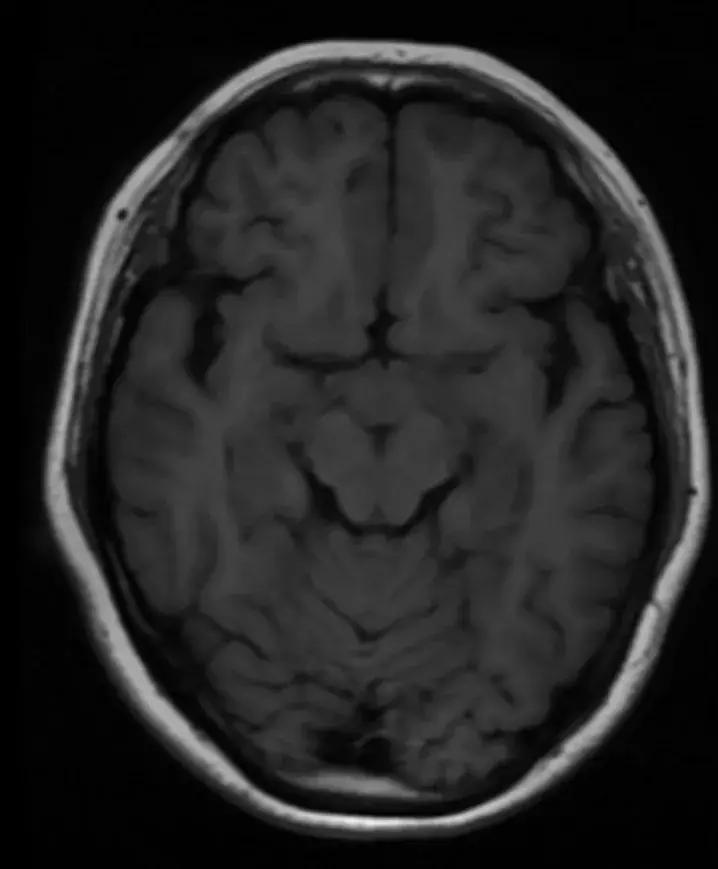

下丘脑见一类圆形异常信号灶,大小约1.6×1.4cm,T2WI呈等略高信号,T1WI呈等信号,DWI呈等信号,增强后明显异常强化,轻度压迫视交叉,FLAR见视交叉及双侧后方视束信号增高。